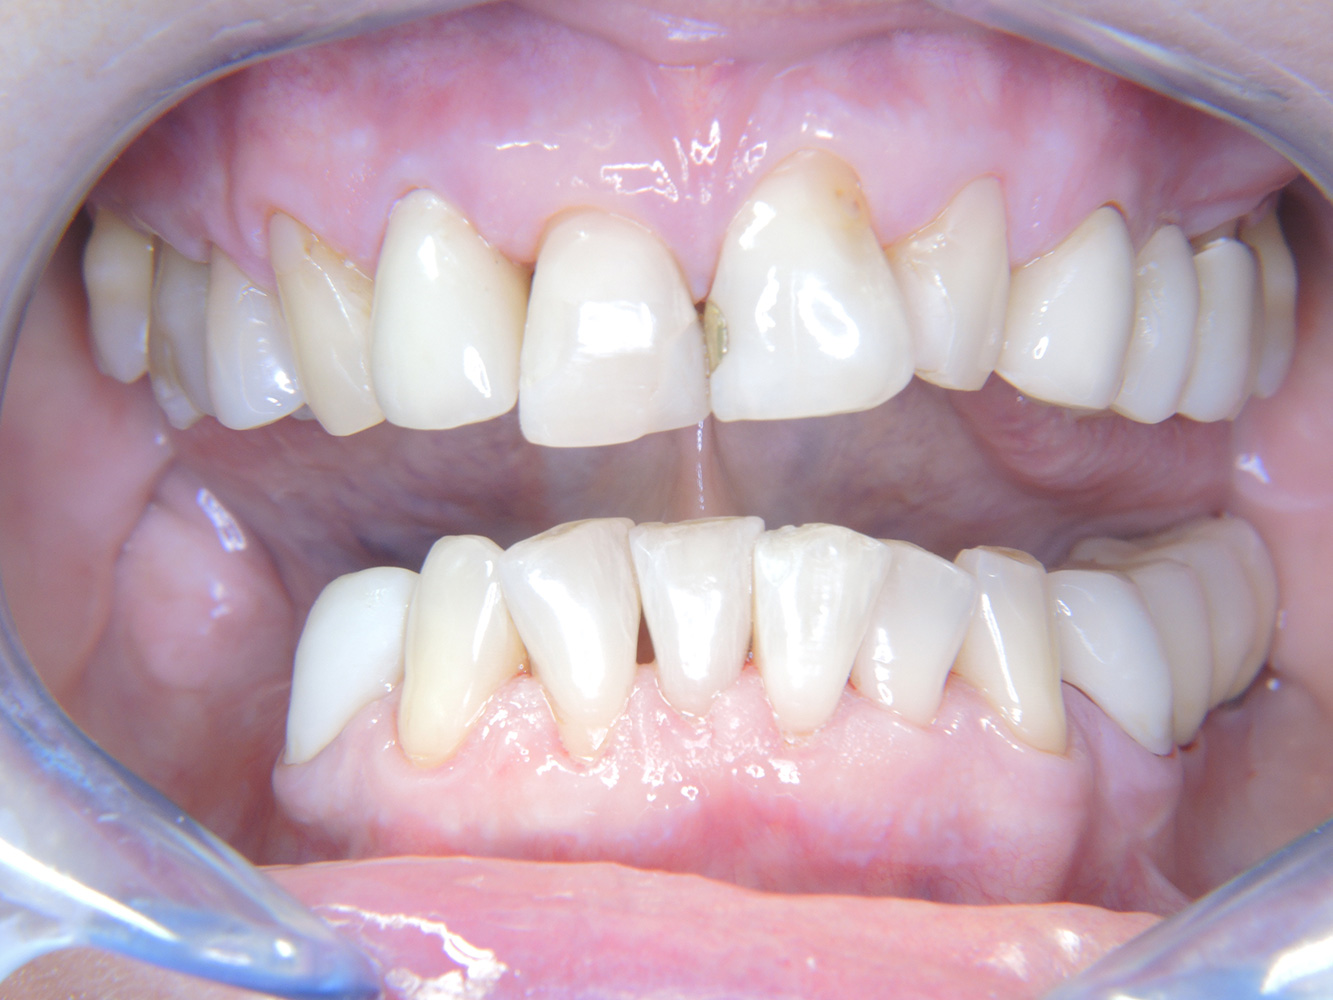

Aunque las condiciones sean estables, no debe descuidarse la motivación y la formación de esta paciente. Hay que prestar especial atención a que aprenda a cómo cuidar los implantes correctamente. Aquí en particular, un buen mantenimiento en casa puede jugar un papel importante en la estabilización a largo plazo de la salud oral y del implante.

Al seleccionar el instrumental, se aplica un procedimiento especial en la zona de los implantes. Para conservar la superficie del implante y, al mismo tiempo, limpiarla con eficacia, es crucial seleccionar los instrumentos y los polvos adecuados, como el uso dirigido de aeropulidores con puntas Paro especiales. La elección de los polvos adecuados puede hacerse según las necesidades y los riesgos, por ejemplo, además del grado apropiado de abrasión, pueden tenerse en cuenta los requisitos alimenticios (como que sean sin azúcar o bajos en sal).